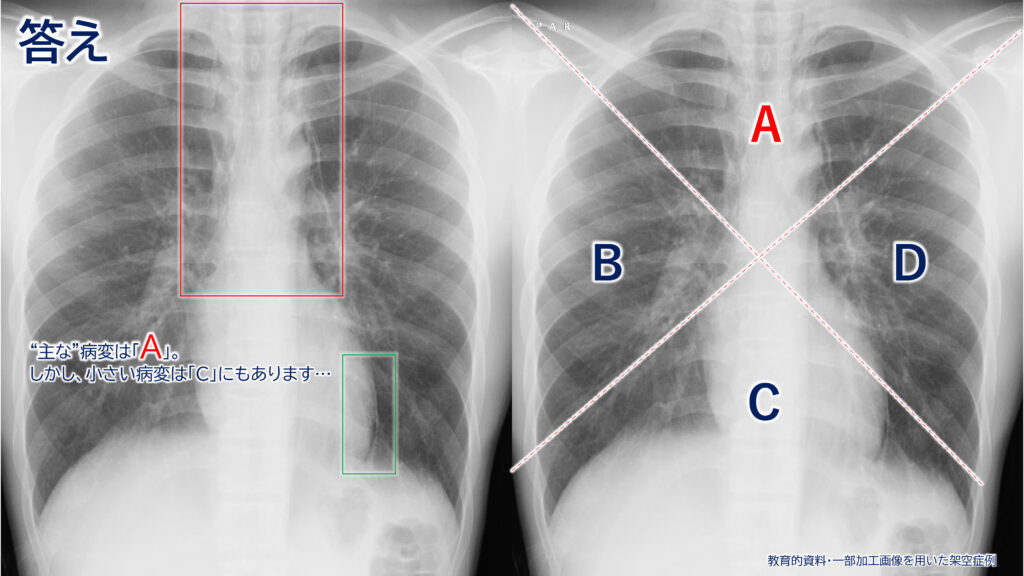

<答えの解説>

所見は実際にはAとCの両方に認められますが、今回は「主な」病変部位を問う趣旨の問題でしたので、正解はAとなります。

(画像分割の都合上、このような形式となりました。)